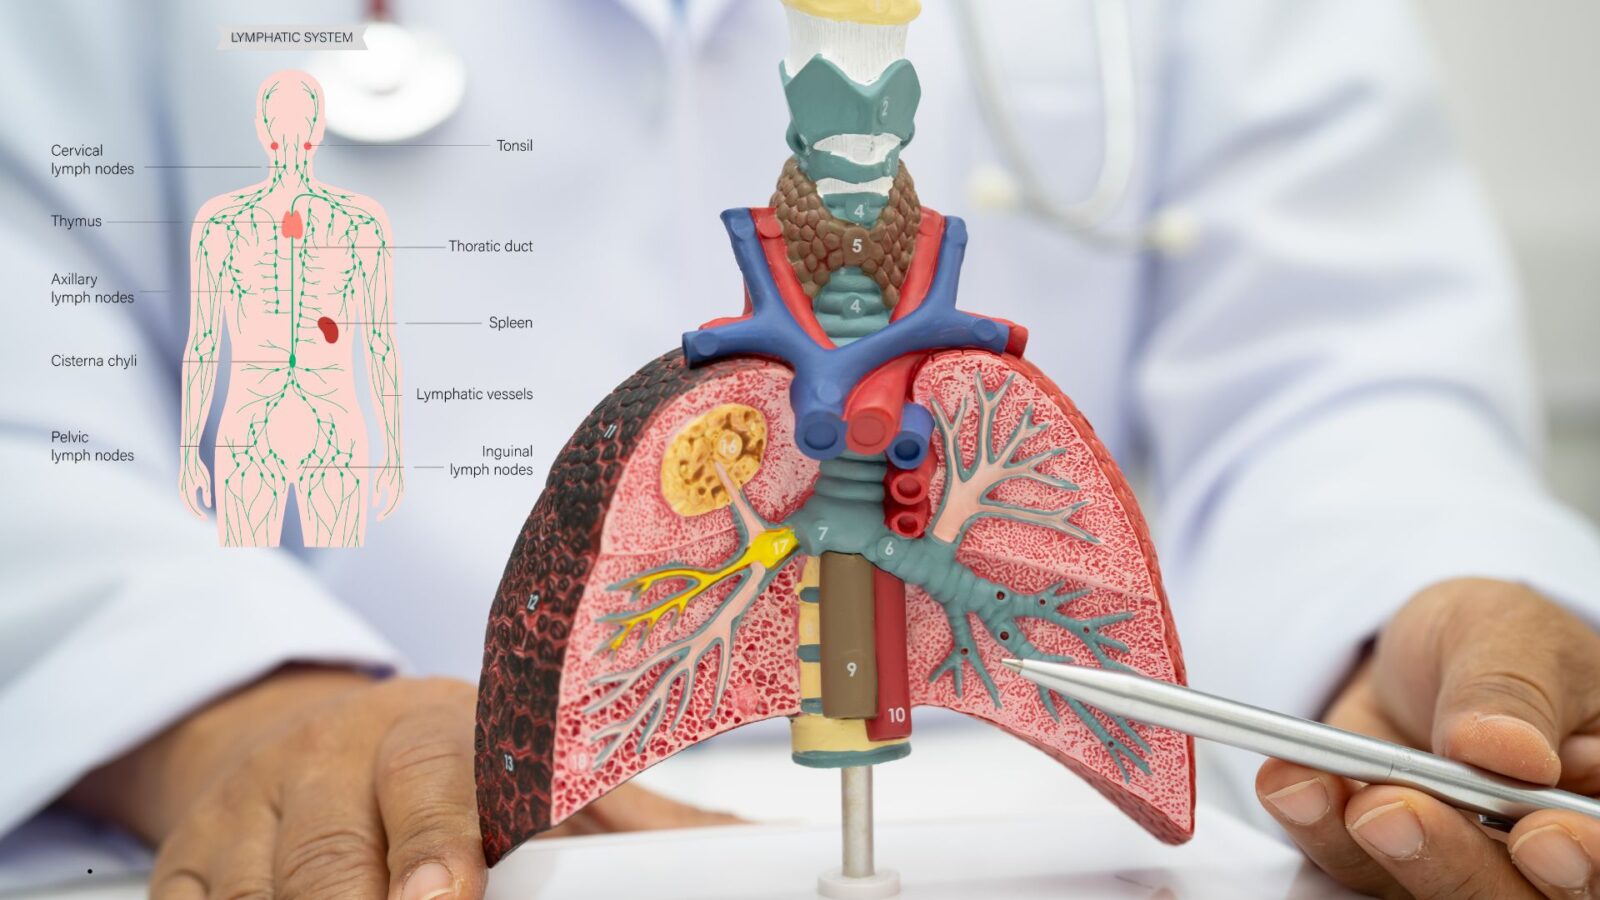

5. Bronkus

Bronkus merupakan percabangan dari trakea.

Setiap paru-paru memiliki satu bronkus utama.

Fungsi Bronkus:

- Menyalurkan udara ke paru-paru

- Mengatur distribusi udara

Bronkus bercabang menjadi bronkiolus yang lebih kecil.

Struktur ini mirip pohon terbalik.

7. Alveolus

Alveolus adalah kantung udara kecil di paru-paru.

Jumlahnya jutaan dalam setiap paru.

Fungsi Alveolus:

- Tempat pertukaran gas oksigen dan karbon dioksida

- Menghubungkan udara dengan pembuluh darah kapiler

Dinding alveolus sangat tipis.

Struktur ini memudahkan difusi gas secara cepat.

Menurut para ahli fisiologi, luas permukaan alveolus sangat besar.

Luasnya bisa mencapai sekitar 70 meter persegi pada orang dewasa.

8. Paru-Paru

Paru-paru adalah organ utama sistem pernapasan.

Organ ini terletak di rongga dada dan dilindungi tulang rusuk.

Paru-paru kanan memiliki tiga lobus.

Paru-paru kiri memiliki dua lobus karena berbagi ruang dengan jantung.

Fungsi Paru-Paru:

- Tempat pertukaran gas secara keseluruhan

- Menjaga kadar oksigen dalam darah